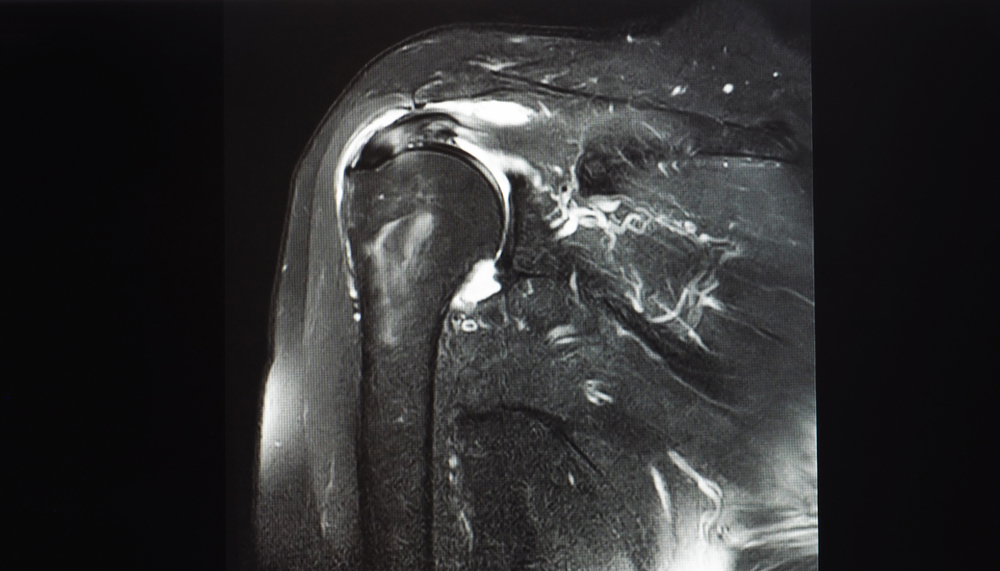

Cisto paralabral do ombro: causas, sintomas e tratamentos